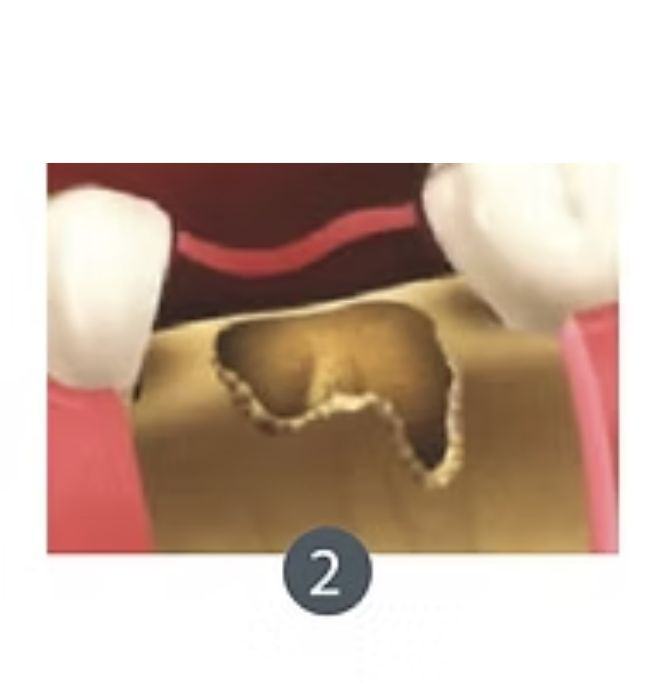

Exodoncia+ Preservación de alvéolo

La exodoncia con preservación del alveolo es un procedimiento dental que combina la extracción de un diente con la protección y preservación del alvéolo dental (la cavidad en el hueso donde estaba el diente) para facilitar futuras restauraciones dentales, como la colocación de implantes dentales.